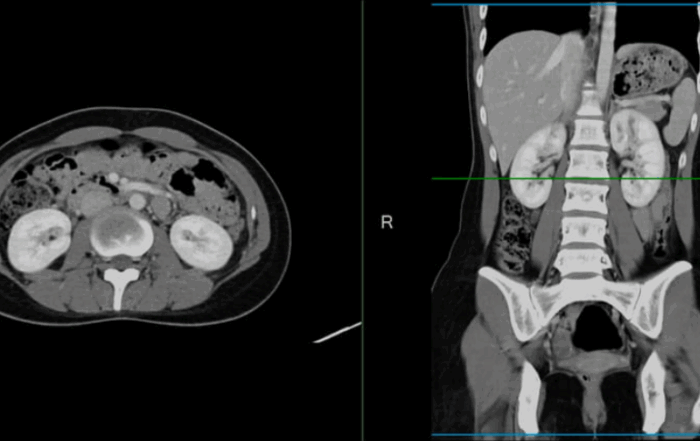

Can A CT Scan Detect Colon Cancer?

Can A CT Scan Detect Colon Cancer? Colon cancer is one of the deadliest forms of cancer, and affects tens of thousands of Americans each year. Unfortunately, it’s also affecting more and more younger people. The best way to fight it? Early detection. Because colon cancer doesn’t have a lot [...]